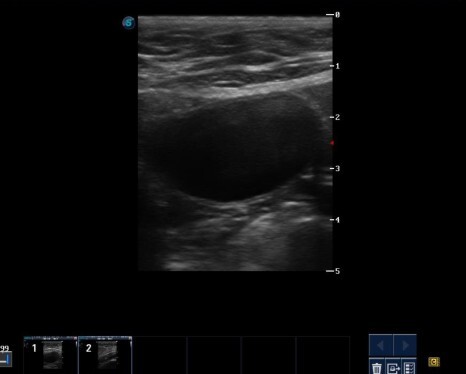

항생제 투약 2주 후 혈뇨가 없어지고 초음파 검사상 방광 상태도 호전된 것을 확인할 수 있었습니다.